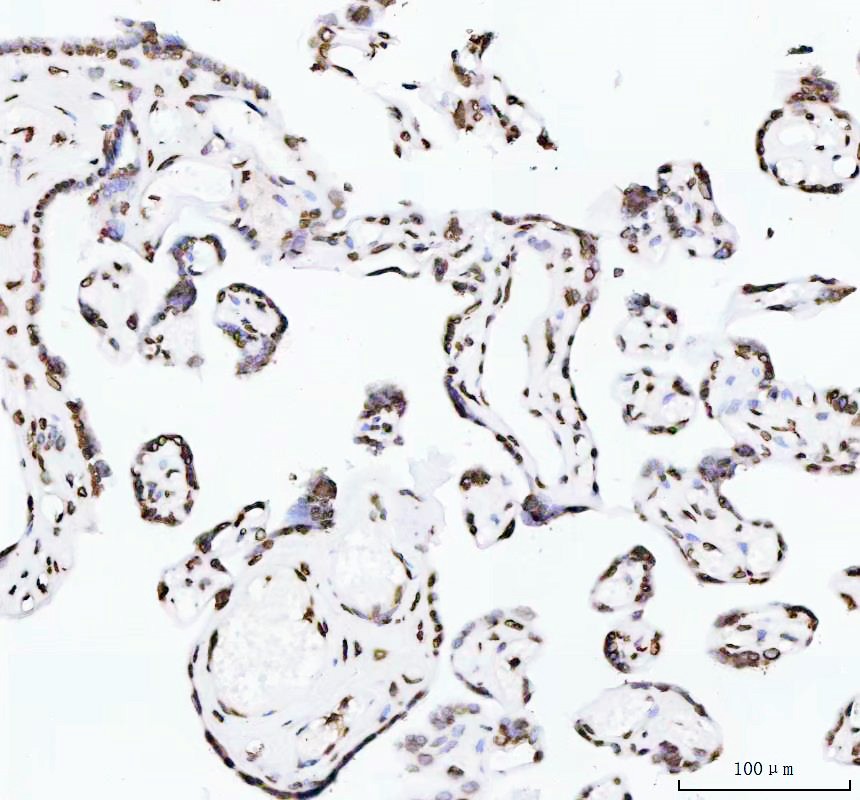

IHC analysis of Histone H4 using anti-Histone H4 antibody (BM4713) .

Histone H4 was detected in a paraffin-embedded section of human placenta tissue. The tissue section was incubated with rabbit anti-Histone H4 Antibody (BM4713) at a dilution of 1:200 and developed using HRP Conjugated Rabbit IgG Super Vision Assay Kit (Catalog # SV0002) with DAB (Catalog # AR1027) as the chromogen.